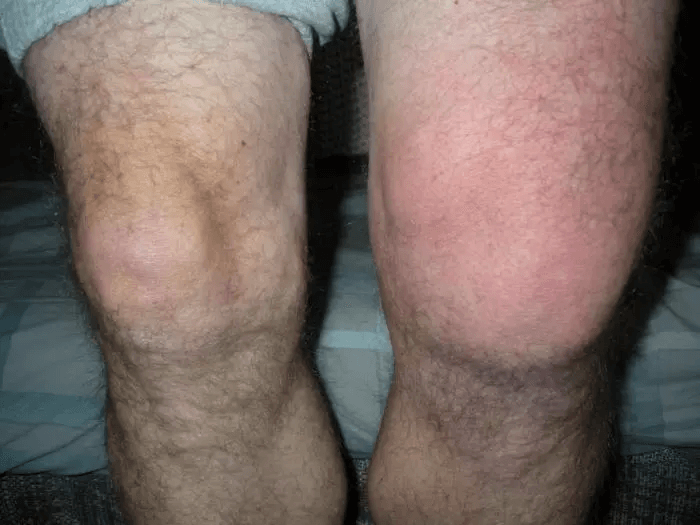

- Otok a zarudnutí kloubu.

Moje kolena se téměř přestala ohýbat. Kotník mi neustále otékal tak, že jsem si nemohl vzít boty. Sotva jsem se pohyboval, ale pokračoval jsem v práci. Nemohl jsem se vzdát divadla a zrušit plánovaná představení. Odborníci mi zakázali práci, hrozí mi invalidní vozík. Ale nikoho jsem neposlouchal, nereagoval jsem problém a zaplatil jsem za to invalidním vozíkem…